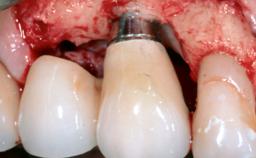

Reconstructive Treatment of a Peri-Implantitis Defect at an Implant in a Mandibular Molar Site

In this case, Mario Roccuzzo utilizes surgical bone regeneration treatment around implant 46 using a bone graft substitute and a connective tissue graft to resolve peri-implant inflammation, reduce the probing depths, and prevent further progression of disease.

A 58-year-old-male patient was referred in February 2007 for implant placement in the right mandibular molar area. Two tissue level implants were inserted at sites 44 and 46, respectively, to support a three-unit fixed dental prosthesis (FDP).